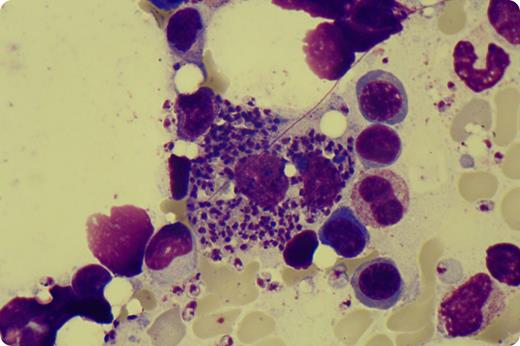

A 49-year-old man from rural Switzerland was diagnosed with chronic myeloid leukemia (CML) in 2007. He eventually underwent 9/10-HLA-matched unrelated stem cell transplantation (HSCT) because of intolerance to first- and second-line tyrosine kinase inhibitors. The early posttransplant period showed complete remission and was uneventful except for mild oral chronic graft-versus-host disease. Ten months after transplantation, when the patient was still under immunosuppressive therapy, we observed progressive pancytopenia. Further investigations included a bone marrow examination, which showed complete remission of CML; however, surprisingly, numerous leishmania amastigotes, both extra- and intracellular, were found within the macrophages. The diagnosis of visceral leishmaniasis by Leishmania infantum was confirmed by polymerase chain reaction, and prompt therapy with liposomal amphotericin B was initiated. The patient’s travel history was retrospectively unremarkable.

Visceral leishmaniasis is a well-known opportunistic infection in severe immunodeficiency, particularly in patients living in areas where leishmaniasis is endemic. It has rarely been seen after HSCT. The 3 potential sources of leishmania transmission in this case could have been the graft itself, transfusions of leishmania-infected blood, or reactivation of a preexisting leishmania infection induced by immunosuppression. Our case illustrates that leishmaniasis can be a cause of severe post-HSCT pancytopenia even in patients living outside areas of endemicity and without a specific travel history.